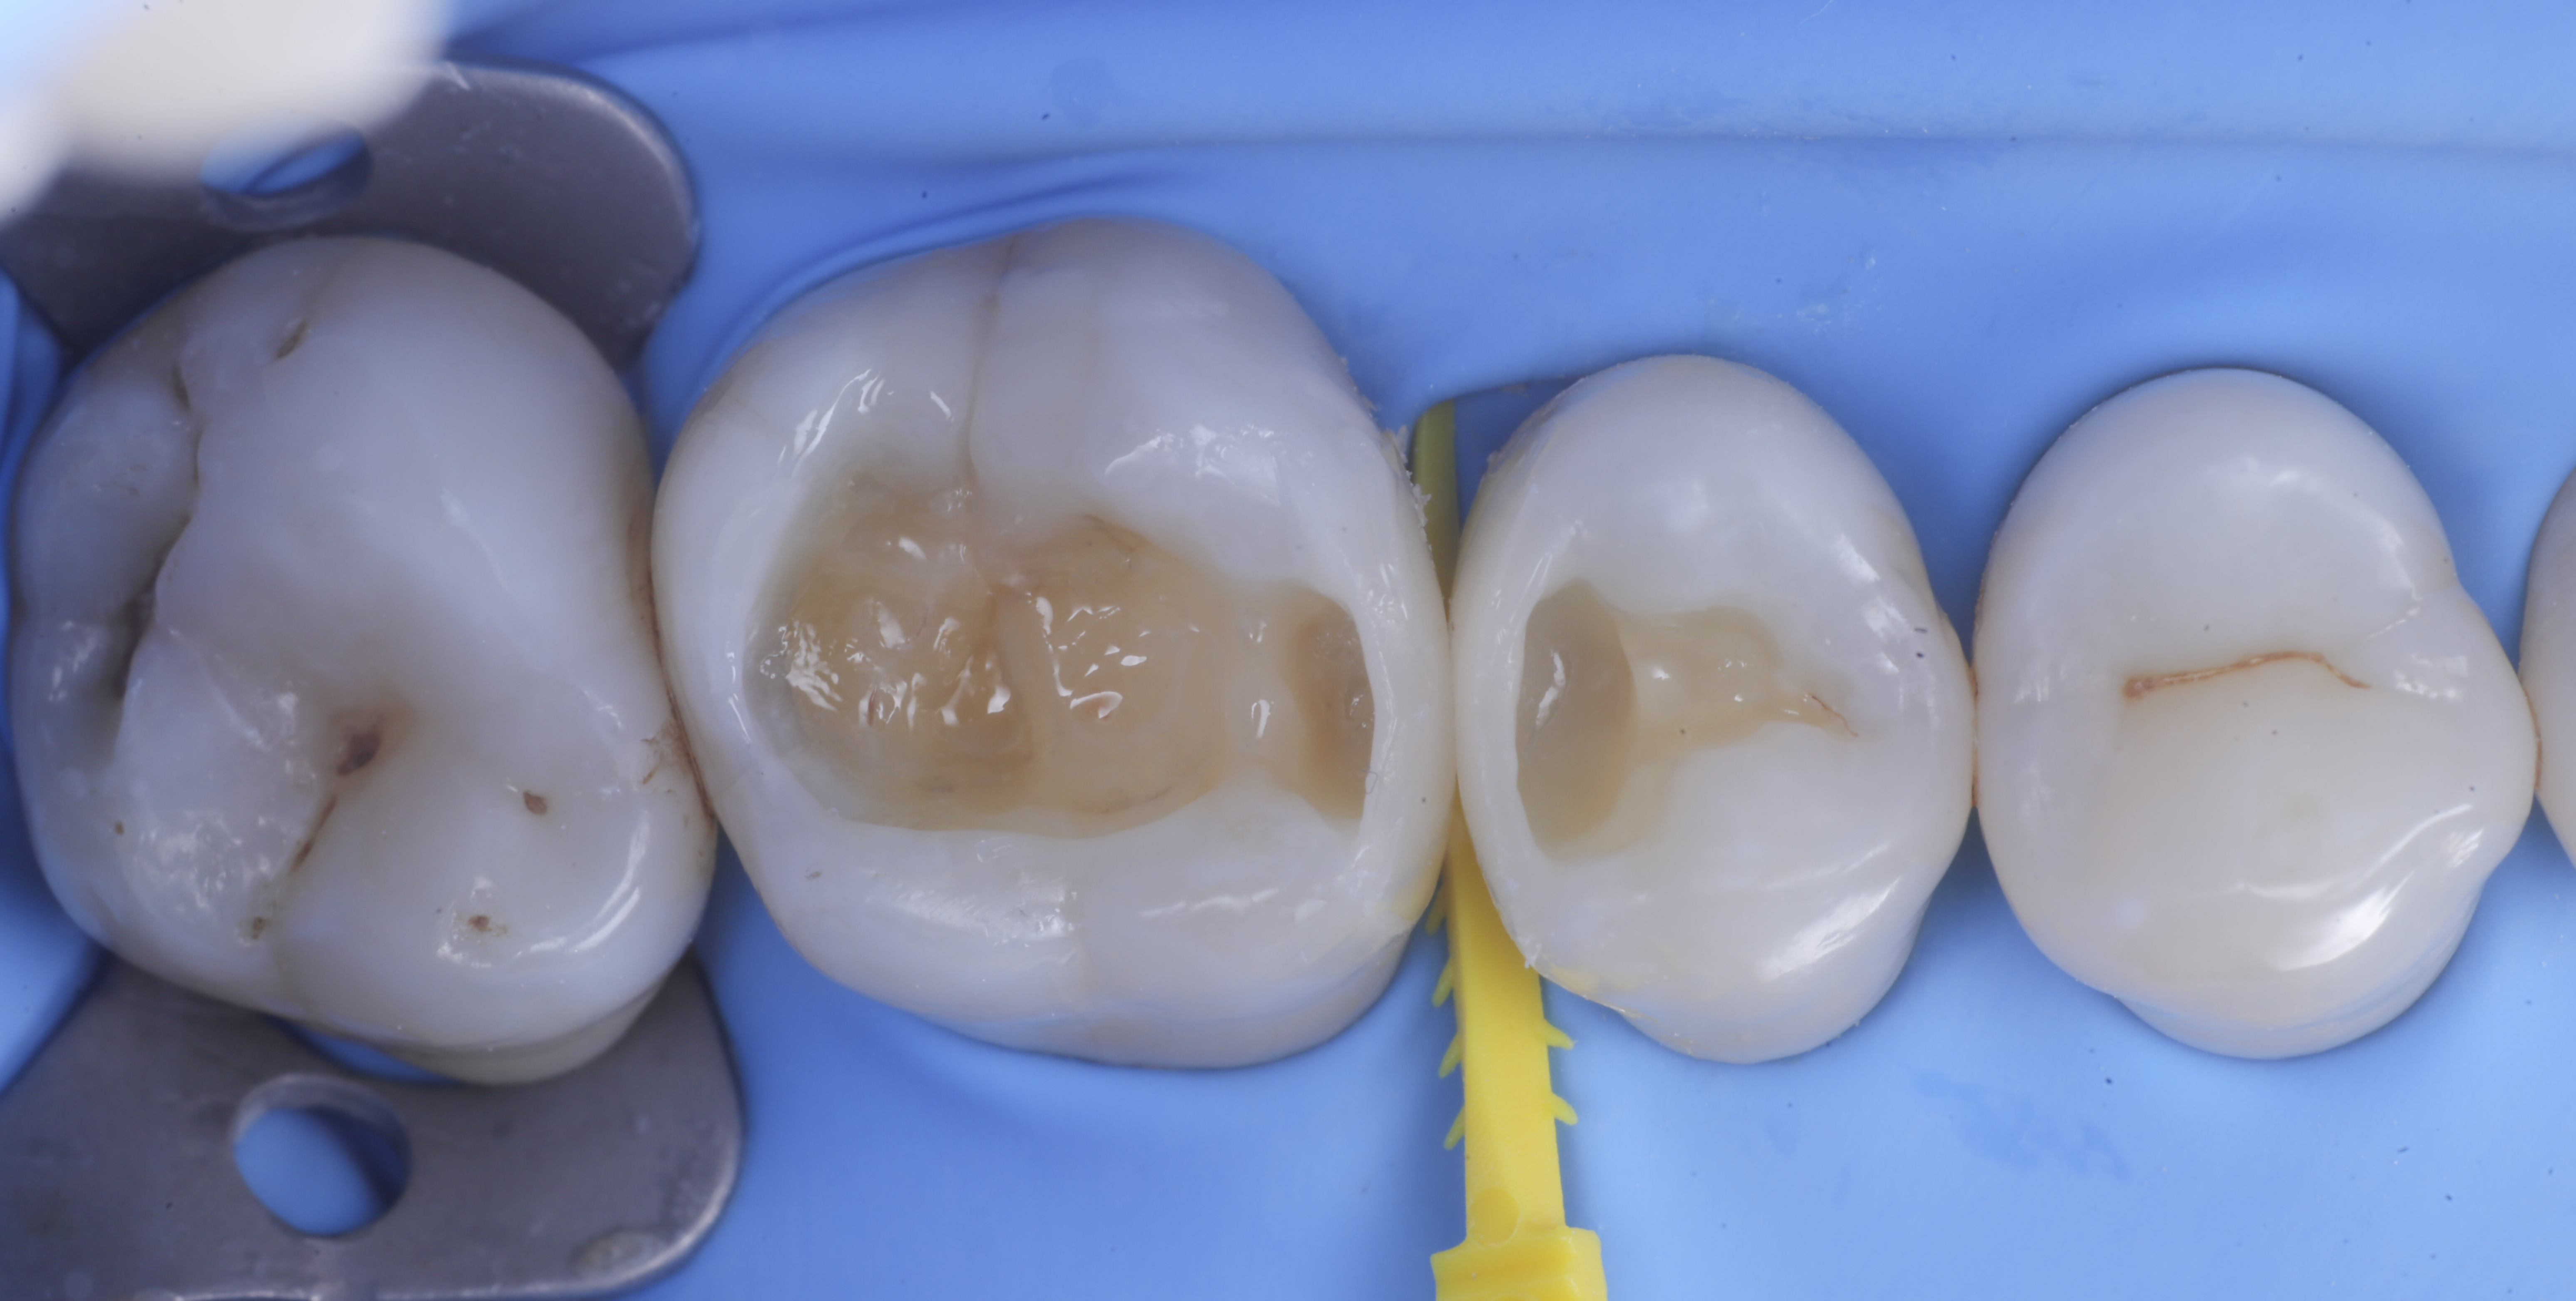

foto 4 Aspetto della chiusura cervicale e sulle pareti assiali dato dalla prima matrice

foto 5 Aspetto della chiusura cervicale e sulle pareti assiali della seconda matrice

Dopo il posizionamento del cuneo, anello e delle due matrici sezionai, selezionate per altezza e raggio di curvatura, si procede con l’applicazione dell’adesivo universale, previa pre-mordenzatura dello smalto.

A questo punto si procede con la stratificazione e modellazione di una delle due pareti inter-prossimali e si polimerizza. Si elimina quindi la matrice della parete appena eseguita sposando l’anello che viene immediatamente rialloggiato.

Successivamente, eliminato lo spessore dato dalla seconda matrice, si procede con la creazione della seconda parete.